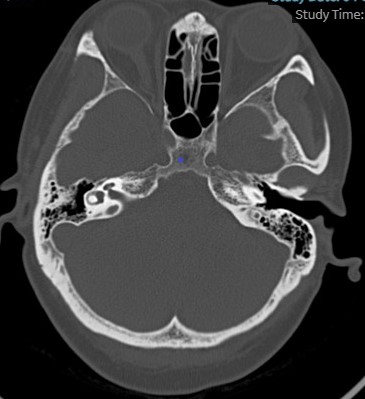

患者头颅CT提示基底节和反射冠多发小斑片缺血灶,双侧基底节钙化灶,排除脑桥小脑角处占位性疾病,骨窗排除中耳炎等疾病。电测听提示双耳听力在20-30分贝之间。